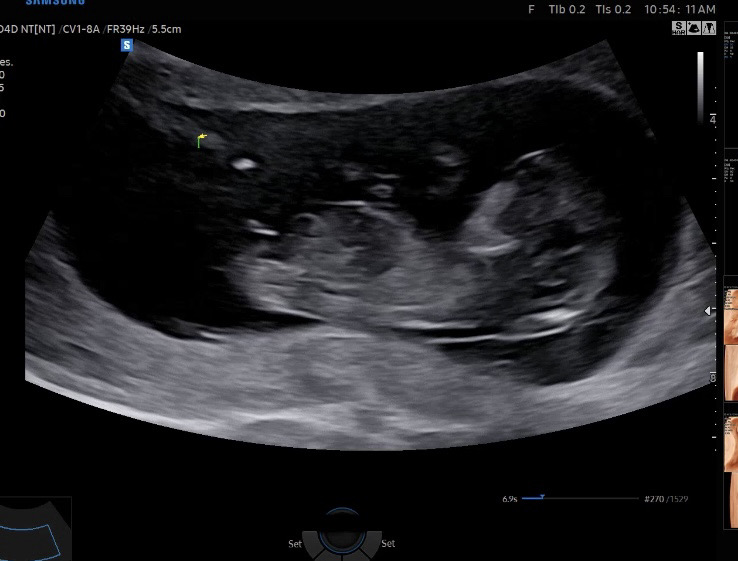

각도법 고수님들 ~!

어때용 ~?!

딸같아요!